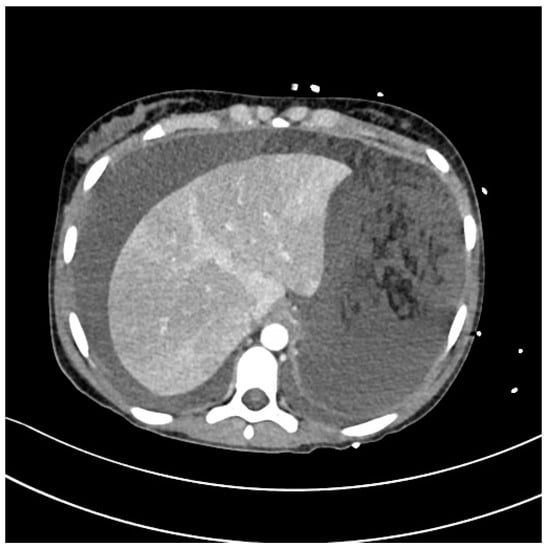

Severe Typhoid Fever Complicated by Superior Mesenteric and Splenic Vein Thrombosis

Veronese, P.; Pappalardo, M.; Maffini, V.; Rubini, M.; Giacometti, A.; Ruozi, M.B.; Cella, S.; Dodi, I. Severe Typhoid Fever Complicated by Superior Mesenteric and Splenic Vein Thrombosis. Infect. Dis. Rep. 2023, 15, 377-385. https://doi.org/10.3390/idr15040038